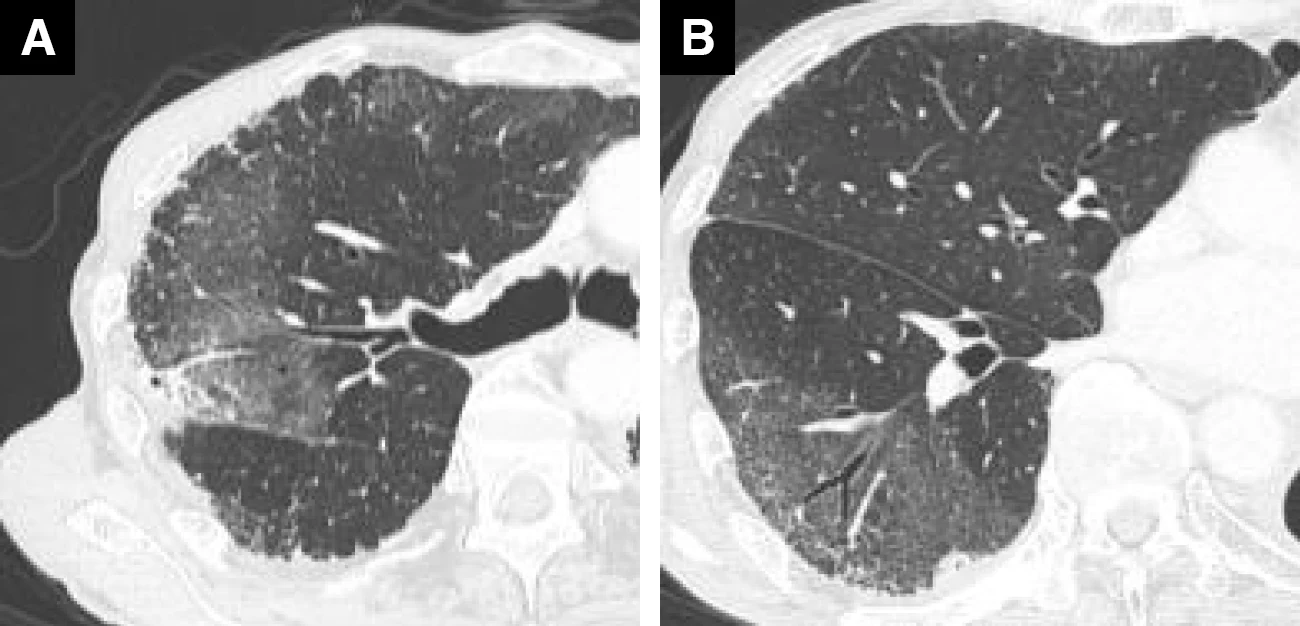

ゲフィチニブ投与症例(82歳、男性、肺腺がん)

A : 薬剤投与前 B : 薬剤投与後(紹介時)

Bでは広範囲のすりガラス影~微細粒状影の出現を認めた

A、B : 薬剤投与後(紹介時)

非区域性に広がるすりガラス影のなかに牽引性気管支拡張所見がみられ、DAD(びまん性肺胞障害)パターンを呈していた